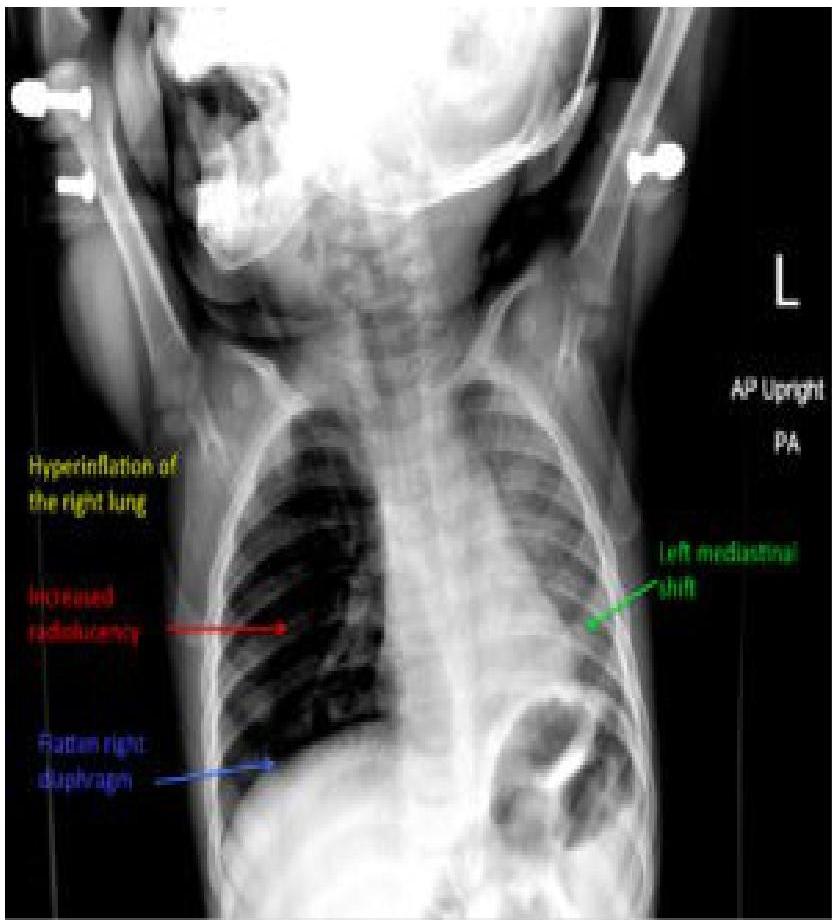

- Bronchial FBA Findings in chest x-ray:

- Hyperinflated lung

- Atelectasis

- Mediastinal shift

- Pneumonia

- Pulmonary abscesses and bronchiectasis (late signs)